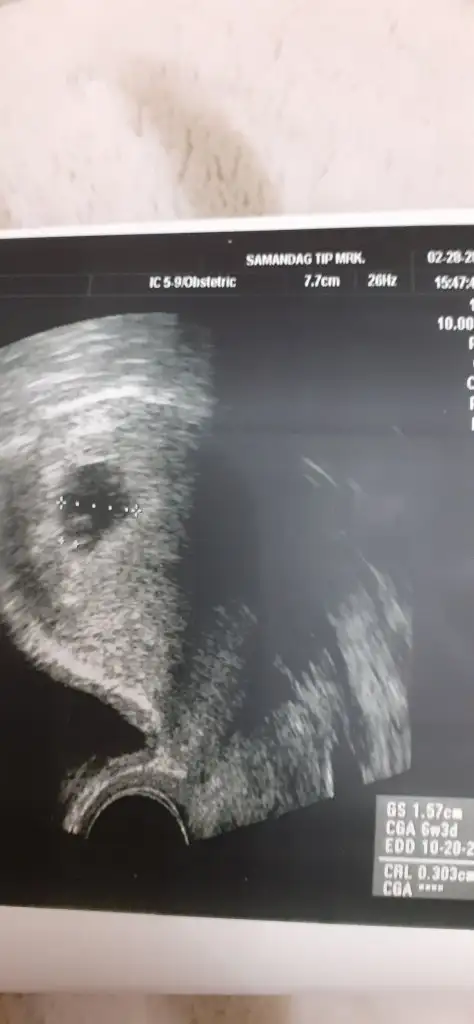

EVET sat 8 ocak :) bebek bile görünmüyordu kesenin içinde. Dün akşam biraz kahverengi lekelenmem oldu. Aslında normal olduğunu okumuştum ama yine de ne olur olmaz doktora gittim. Farklı bi doktordu. Doktor beni yatırdı. Bişey sormadan direk sesi açtı. Ben de şok oldum. :) Dediğiniz gibi çok stresli ve gergindim. İlk hamileliğim olduğu için tecrübesizlik de var tabi. Bişey soramadım heyecanla. Daha önce 10 gün kadar geriden çıkmıştı crl. Şimdi tam 7 haftalık göründü. Sadece 3 gün geriden geliyor. Allahın izniyle o da toparlanır diye inanıyorum :) Dediğim gibi Rabbim herkese hayırlısıyla kucağına almayı nasip etsin :)

Ramzi metodu diye bir sey var bebegin kesedeki vajinal ya da karindan fotosuna gore yorumlaniyor. Ben baktim erkek gozukuyor :) %85 dogruluk payi varmis ornek olarak atayim kendiminkini. Vajinal usg ile cekilmis bir foto ve kesede sağa yerlesmis. Bu aslinda solda oldugu anlamina geliyormus. Solda olanlar da erkek oluyormus.

%85 tutuyormus acilmis konular var bunla ilgili buralarda bakabilirsiniz :) tek onemli nokta vajinal mi abdominal mi bakıldığı :) saglikli olsunlar yeter ki

Vajinal olunca tersini mi düşünmek lazım anlamadım o kısmı. Bu vajinal